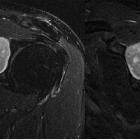

Peripheral

schwannoma mimicking a bone tumour. Hyperintense, well-defined lesion on T2-WI